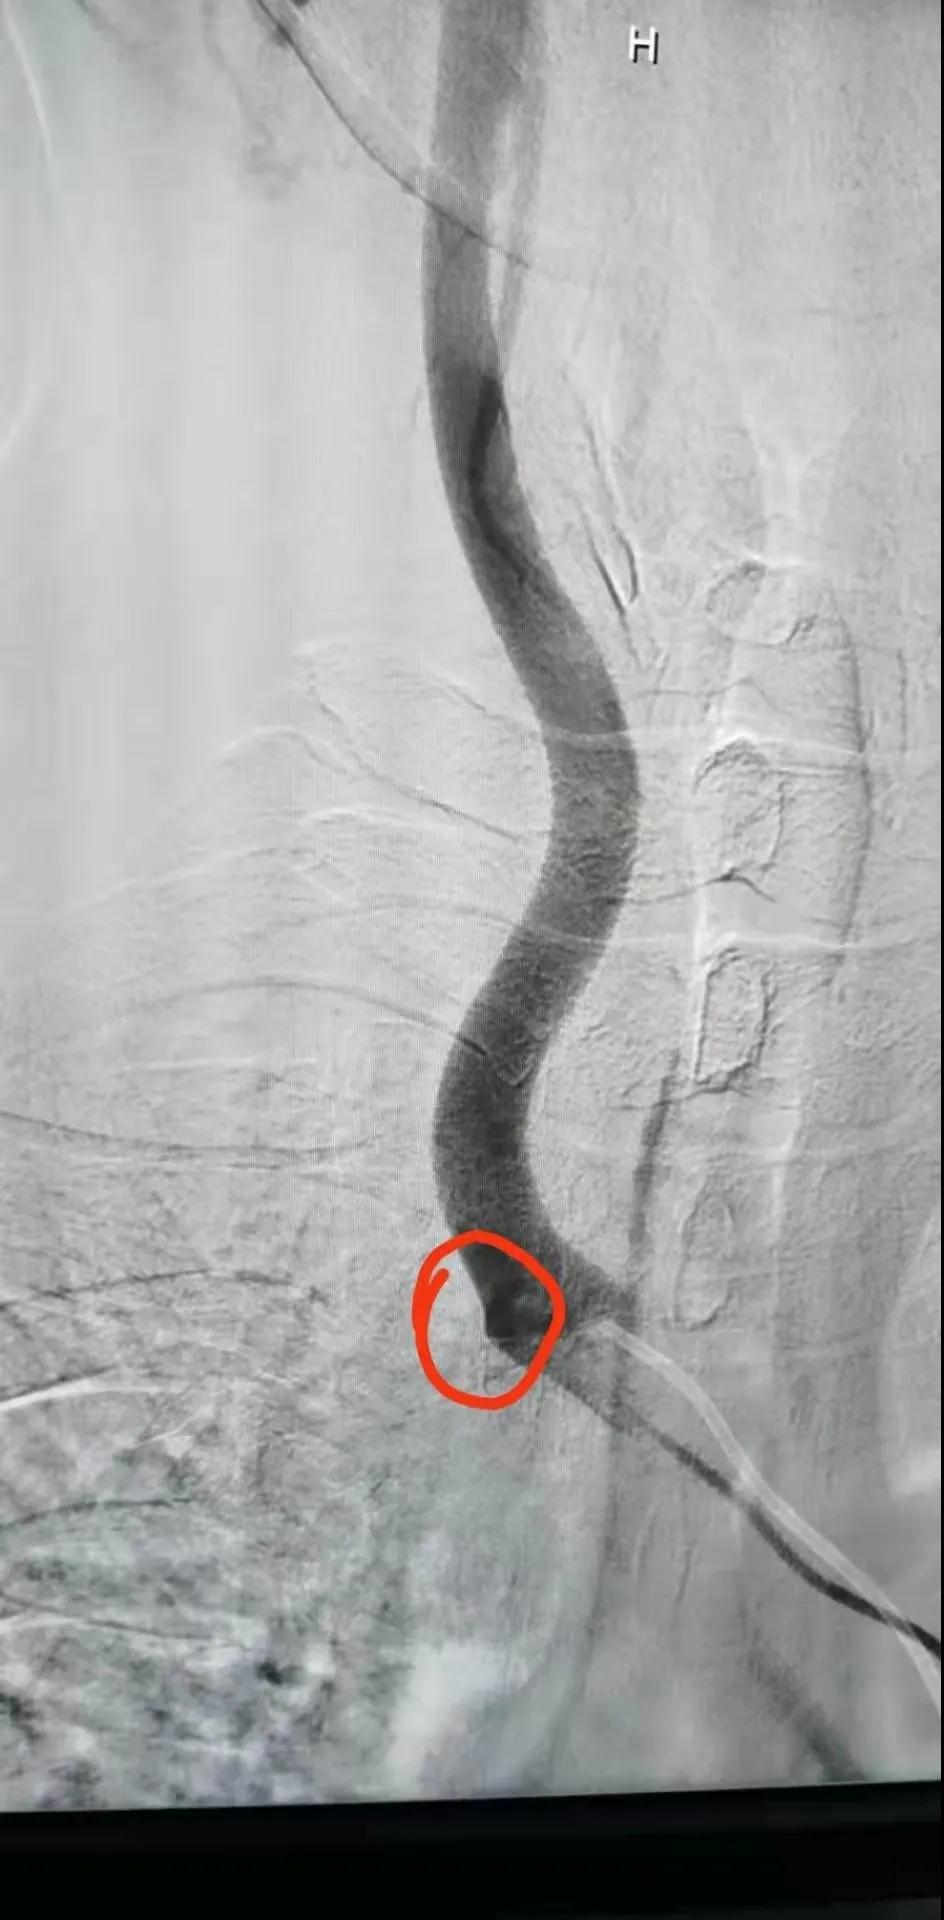

近日,濱海康達醫院成功為一位鎖骨下盜血綜合癥伴右鎖骨下動脈閉塞患者,實施DSA下右鎖骨下動脈球囊擴張+支架置入術,該手術的成功,再一次刷新了濱海康達醫院開展微創介入治療的新病種,為更多患者帶來健康福音。

家住揚州寶應的王先生,男,52歲,吸煙喝酒多年,已反復暈厥多次,先后到北京和當地醫院求診,均因病情復雜而被拒。后經親戚介紹至濱海康達醫院求診,介入科魏棟主任醫師接診后,行相關檢查并結合此前北京檢查病例資料,臨床診斷為:鎖骨下盜血綜合癥伴右鎖骨下動脈閉塞,擬實施DSA下右鎖骨下動脈造影+球囊擴張+支架植入術。

右鎖骨下動脈未顯影

開口處閉塞

造影見大斑快堵塞開口